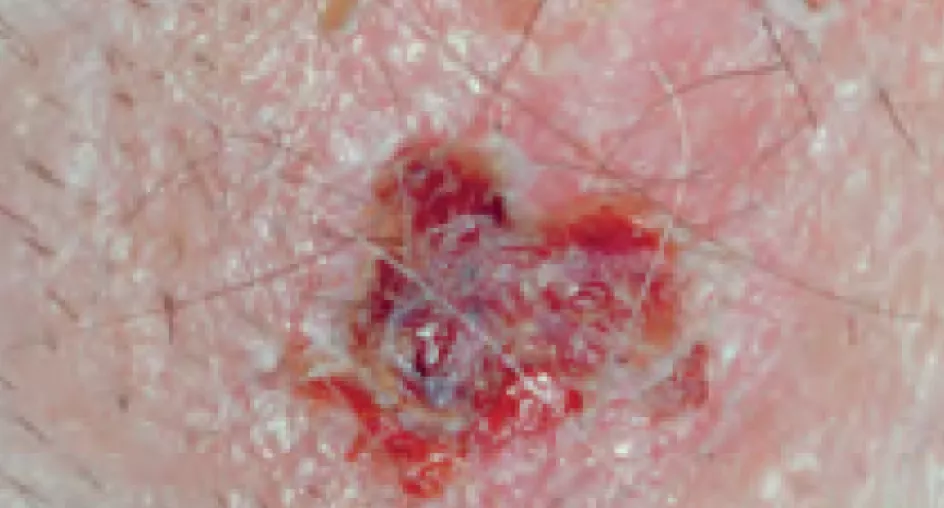

Некоторые виды токсичности гидроксикарбамида со стороны кожи отражены на рис. 2.

Актинический кератоз и немеланомные опухоли кожи

Частота предраковых и раковых осложнений терапии гидроксикарбамидом составляет около 4%. Злокачественные опухоли, ассоциированные с терапией гидроксикарбамидом, включают базальноклеточную карциному, плоскоклеточный рак и карциному клеток Меркеля [6].

Актинический кератоз

Плоскоклеточная карцинома

Рисунок 2. Кожные проявления токсичности гидроксикарбамида